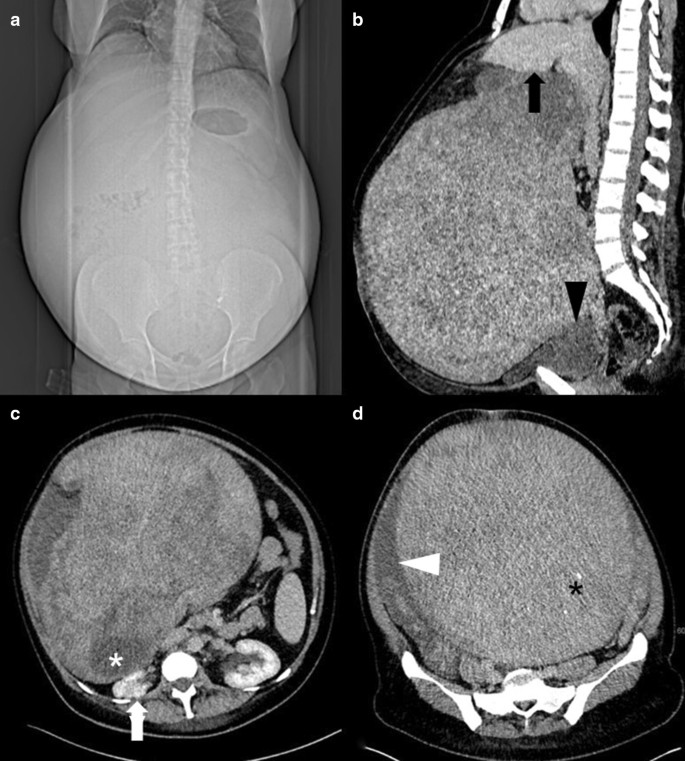

In our clinic, a preliminary physical examination was performed, which indicated good general condition and no evidence of pallor or pedal edema. The patient’s preoperative body mass index (BMI) was 32.1 kg/m2. Her abdomen was enormously enlarged and pendulous with flank fullness on both sides. An irregular mass arose from the pelvis up to the xiphisternum and was not discernible owing to abdominal wall obesity. There were no hernias or abdominal varices. Renal angle fullness was not observed. Because of the patient’s anxiety, a vaginal examination could not be performed. Transabdominal ultrasound showed a huge intraabdominal mass. The right kidney showed impaired cirrhosis, while the left kidney showed compensatory enlargement. A small amount of ascites was observed. An urgent computed tomography (CT) scan was performed revealing a large tumor that occupied the abdominopelvic cavity completely. On the CT scan, the mass measured 32 × 27 × 34 cm (intralesion diameter) and could not be visibly separated from the uterine cavity, bladder, or liver (Fig. 1). The tissue of origin and extent of tumor invasion remained unclear. The mass appeared heterogeneous, containing cystic and necrotic areas along with solid components. It compressed the intestines, right kidney, and both ureters. The spleen was mildly enlarged. The hepatorenal recess (Morison’s pouch) showed minimal ascites. No lymph nodes were observed. Due to the slow growth of the tumor, few ascites, and negative lymph nodes, malignancy was highly unlikely.

CT reveals extensive abdominal enlargement in the scout view (a). Sagittal CT reconstruction depicts a giant tumor in contact with the liver (black arrow, b) and with the urinary bladder (black arrowhead, b). The mass contains necrotic components (white asterisk, c), as well as small calcifications (black asterisk, d). The preoperative situs shows compression of the right kidney (white arrow, c) and ascites adjacent to the tumor (white arrowhead, d)